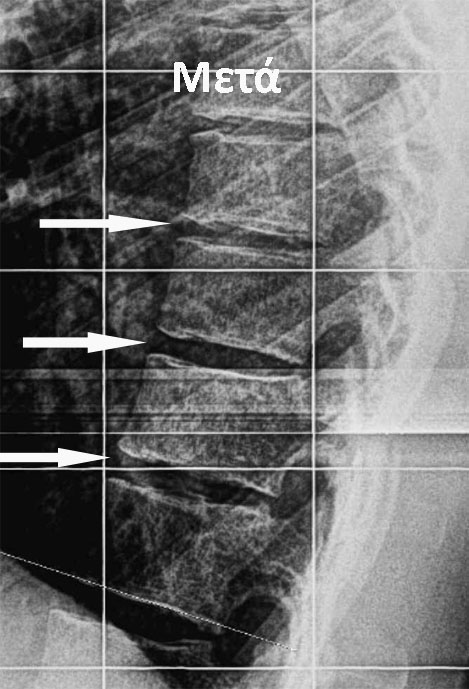

Πριν

Μετά

Η υπερέκταση που δημιουργούν στο σώμα οι ασκήσεις αλλάζουν, εξαιτίας της πλαστικότητας των δίσκων, το σχήμα των πρόσθιων τμημάτων των μεσοσπονδύλιων δίσκων. ***

Ο κηδεμόνας εφαρμόζεται ώστε να διατηρήσει το αποτέλεσμα αυτό των ασκήσεων, σε βάθος χρόνου, διατείνοντας τους συνδέσμους.